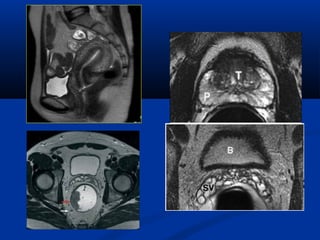

U maùu vuøng haømU maùu vuøng haøm

(T)/(T)/ Daõn tónh maïchDaõn tónh maïch

caûnh ngoaøi (T)caûnh ngoaøi (T)